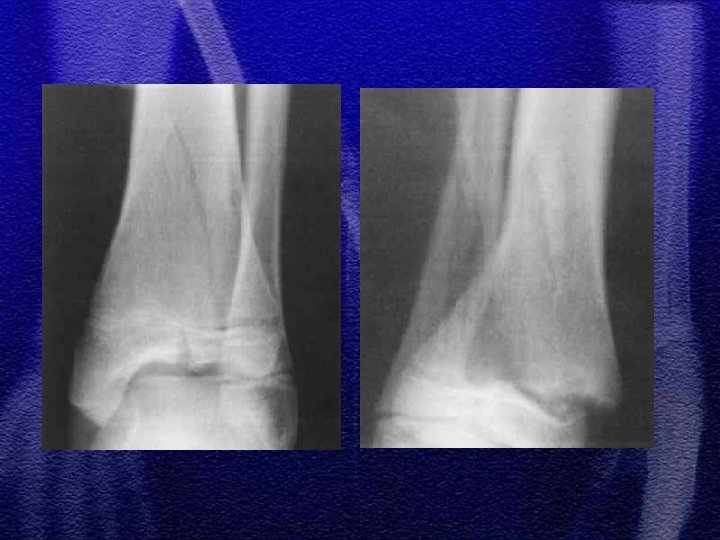

§ Złuszczenia nasady bliższej wyjątkowo rzadkie, obarczone powikłaniem pod postacią zaburzenia wzrostu kończyny co może prowadzić do znacznych odchyleń osi § Złamania bliższej przynasady mogą powodować podobne powikłania

§ U dzieci małych mogą wystąpić kłopoty diagnostyczne, ponieważ obrzęk w obfitej w tkankę tłuszczową kończynie jest niezauważalny, dziecko raczkuje, przy złamaniach podokostnowych lekko utyka chodząc, dlatego zdarza się że rozpoznanie jest opóźnione § Leczenie - gips udowy 2 -4 tyg. § U dzieci zdarzają się, choć rzadko, złamania marszowe